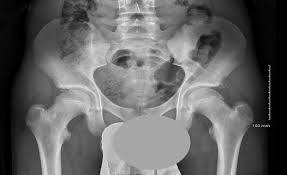

What is pelvis avulsion fracture?1. An avulsion fracture occurs when a tendon or ligament attached to a bone pulls against it and fractures off a piece of the bone. A pelvic fracture is a disruption of the bony structures of the pelvis. Your doctor might recommend that you use crutches to keep weight off the hip while it heals. A pelvic avulsion fracture is where the tendon comes away from the bone, often taking a piece of bone with it.

Pelvic Avulsion Fracture Symptoms Causes And Treatment from www.sportsinjuryclinic.net In the pelvis, the newly formed secondary centers of ossification, the apophyses, are the most likely portions of the bone to avulse. In adults, the ligaments and tendons tend to be injured first, whereas in children the bone may fail before. Physical therapy may also help a fracture heal more quickly than immobilization alone. Pelvis injuries range from the benign to life threatening. Your doctor might recommend that you use crutches to keep weight off the hip while it heals. Avulsion fractures are more common in children than in adults. Your doctor might recommend that you use crutches to keep weight off the hip while it heals. Aiis and ischial tuberosity fractures are at increased risk of developing future pain and nonunions, respectively.

A pelvic fracture is a disruption of the bony structures of the pelvis. Avulsion fractures are most common in the pelvis. Detailed explanation of pelvis avulsion fracture or avulsion fracture of the pelvis. Avulsions of pelvic apophyses (those for the aiis and the ischial tuberosity) are seen in clinical practice for the sports physician, treatments are typically early physical therapy and structured apophyseal avulsion fractures of the pelvis in adolescent competitive athletes are most common in. Pelvic floor physical therapy plays a key role in calming and desensitizing the central nervous system, and as such, it is considered the gold standard treatment. In this series, nearly all pelvic avulsion fractures (97%) were managed successfully with a conservative approach. The hip, elbow and ankle are the most common locations for avulsion fractures in the young athlete. Falguni vashi pt, dpt, prpc founder of pelvicure physical therapy. An avulsion fracture is an injury to the bone in a location where a tendon or ligament attaches to the bone. An avulsion fracture occurs when a tendon or ligament attached to a bone pulls against it and fractures off a piece of the bone. Physical therapy can also help improve strength and decrease your risk for loss of function. Patients and families need to be counseled about this. Your doctor might recommend that you use crutches to keep weight off the hip while it heals.